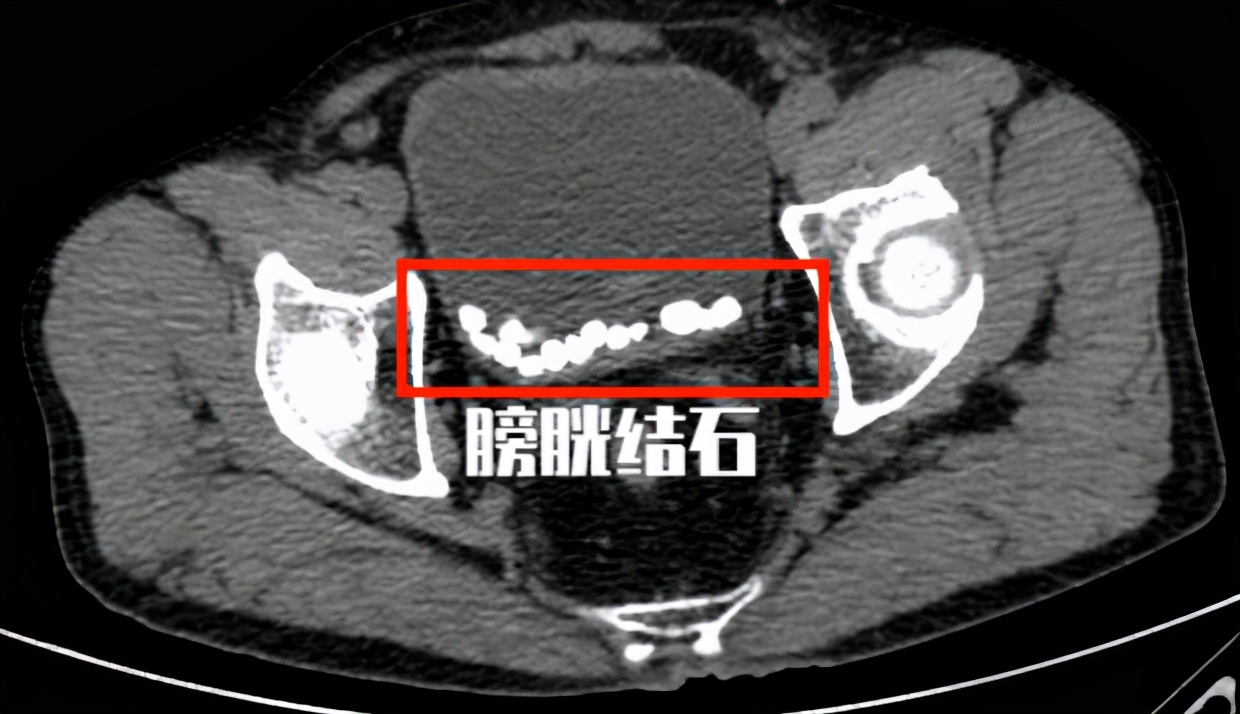

老王今年74岁, 3个月前自诉突发排尿困难,尿线变细来医院就诊 。在当地医院查CT提示 前列腺增生伴膀胱结石,最大膀胱结石体积1.8cm。 粗略估计了一下老王膀胱里的膀胱结石大概不下20颗。老王很奇怪, 为什么他有膀胱结石,而且有这么多结石,但是为什么自己什么感觉都没有呢?

老王的膀胱结石